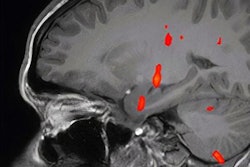

Neuroradiological manifestations of COVID-19 differ by the severity of the disease, according to a literature review published August 29 in Academic Radiology. The results could help clinicians better understand neurological expressions of COVID-19.

"Cranial nerve abnormalities appear exclusive to mild infection, with a high degree of olfactory tract involvement, while hemorrhagic events are more common in severe infection," the team concluded. "Notably, ischemic infarction was equally prevalent in both mild and severe COVID-19 infection. Healthcare providers treating COVID-19 patients should be aware of these potential complications and consider neurological assessment and neuroimaging studies when indicated."